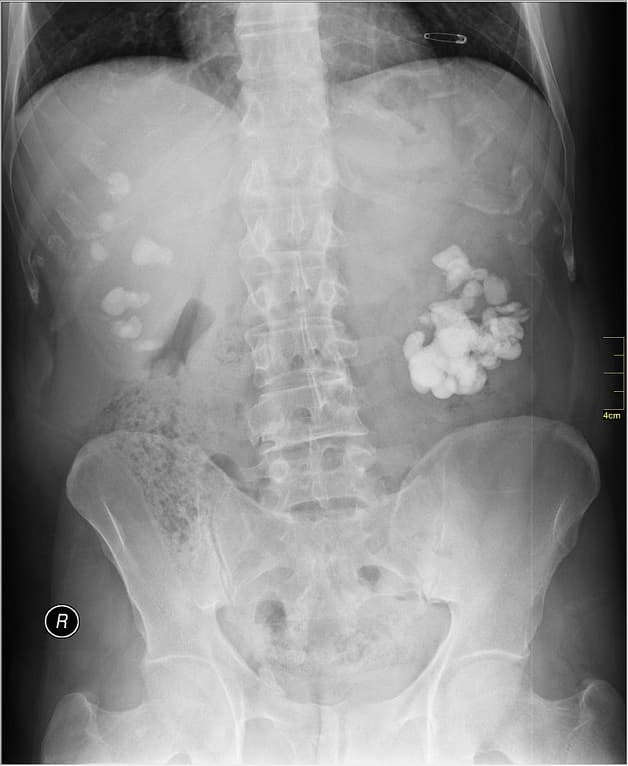

6.5. Chụp X-quang (KUB)

Người bệnh sẽ được yêu cầu chụp X-quang niệu quản, thận, bàng quang để giúp xác định trong hệ tiết niệu có sỏi hay không. Đây là phương pháp tiết kiệm chi phí, dễ thực hiện nhưng có thể sẽ không phát hiện ra một số loại sỏi không cản quang.

6.6. Chụp cản quang đường tĩnh mạch để phát hiện bệnh sỏi bàng quang

Chuyên gia sẽ tiêm chất cản quang vào tĩnh mạch của người bệnh. Thuốc cản quang sẽ đi đến hệ tiết niệu từ thận xuống bàng quang và niệu quản. Hình ảnh đường đi của chất cản quang qua các bộ phận trong hệ tiết niệu sẽ được thu lại bằng máy chụp X-quang.

Chụp X-quang sẽ giúp thu thập các hình ảnh về tình trạng của sỏi